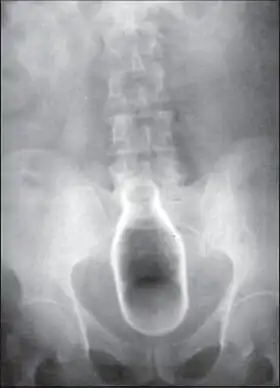

Typiquement plusieurs radiographies sont requises pour que l'on puisse localiser précisément le corps étranger et déterminer jusqu'à quelle profondeur il a avancé. Généralement, on utilise les rayons X à cette fin. Les corps étrangers composés de matériaux à bas contraste, comme par exemple le plastique, peuvent faire indiquer un examen échographique ou tomodensitométrique (TDM, couramment dit « scanographie »)[18]. L'imagerie par résonance magnétique (IRM) est contre-indiquée, surtout lors d'un corps étranger inconnu. L'endoscopie, dont l'emploi peut aussi servir des fins thérapeutiques, aide à l'identification et à la localisation de l'objet coincé dans le rectum[19].